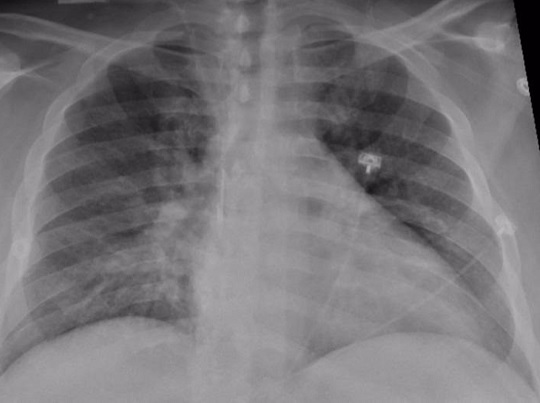

El tejido pulmonar de pacientes que sufrieron el Covid-19 de forma grave muestra una buena recuperación en la mayoría de los casos. Así lo reveló un estudio realizado por el centro médico universitario de Radboud que ahora se ha publicado en la revista 'Clinical Infectious Diseases'.

El estudio, dirigido por el neumólogo Bram van den Borst, incluyó a 124 pacientes que se habían recuperado de infecciones agudas por COVID-19. Visitaron la clínica de cuidados posteriores corona del centro médico de la universidad de Radboud, en Países Bajos. Los pacientes fueron examinados por tomografía computarizada y una prueba de función pulmonar, entre otros análisis.

Después de tres meses, los investigadores hicieron un balance, que reveló que el tejido pulmonar de los pacientes se estaba recuperando bien. El daño residual en el tejido pulmonar fue generalmente limitado y se observa con mayor frecuencia en pacientes que fueron tratados en la UCI.